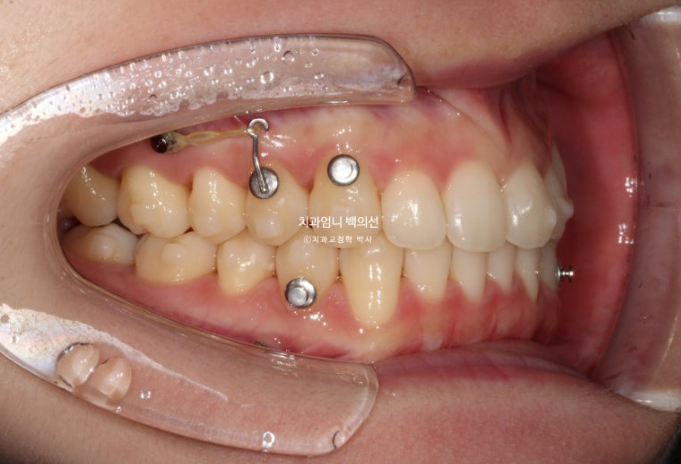

23년 8월부터 1년동안 60여개의 장치를 낀 모습입니다.

필요한 곳에 교정용 나사인 미니스크류를 심고 진행해야 효율이 좋습니다.

24.09

중심선이 처음에 비해 좋아졌으나 아직 불일치가 보입니다.

환자가 직접 뺏다꼈다 하는 고무줄 처방도 들어갔고 첫번째 세트와 70개 장치를 모두 낀 후 모습은 다음과 같습니다.